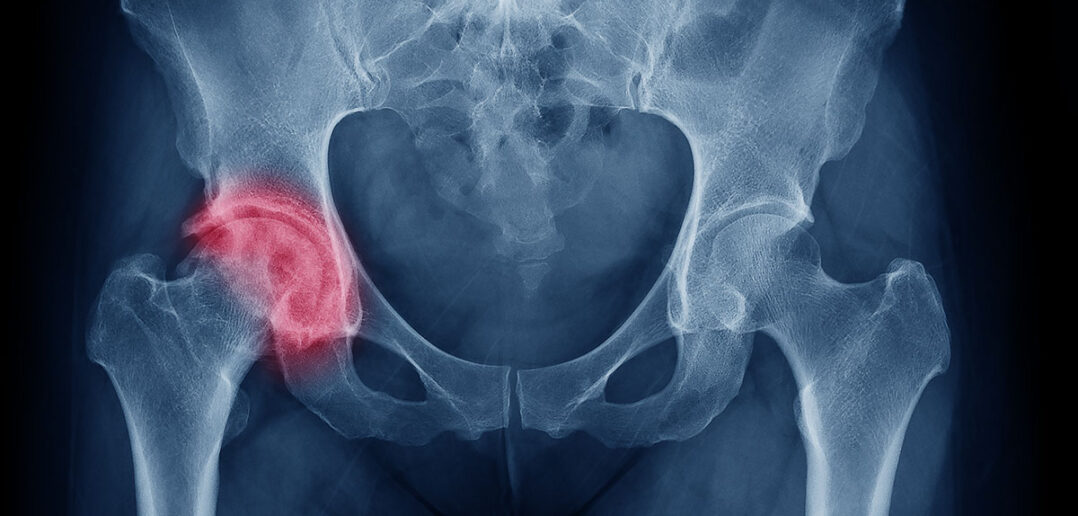

Hüftarthrose: In dieser Serie stellt Stephan Müller die besten Übungen für Kunden mit unterschiedlichen gesundheitlichen Problemen vor. Im dritten Teil stehen das Hüftgelenk und seine durch mangelnde bzw. ungünstige Bewegungen verursachten funktionellen Defizite, insbesondere die Hüftarthrose, im Mittelpunkt.

Wie entsteht Hüftarthrose?

Das Hüftgelenk ist neben dem Kniegelenk das am häufigsten von Verschleißerkrankungen betroffene Gelenk des Menschen. Arthrose ist eine degenerative Gelenkserkrankung, die vorwiegend bei einem Missverhältnis zwischen Beanspruchung und Beschaffenheit bzw. Leistungsfähigkeit der einzelnen Gelenkanteile und -gewebe entsteht. Eine primäre Arthrose entsteht meist im Alter ab ca. 50 Jahren. Hier kann der Stoffwechsel im Gelenkknorpel seine Gewebeerhaltungsfunktion nicht mehr erfüllen und der hyaline Knorpel verschleißt bereits unter funktioneller Belastung. Bei dieser Form der Arthrose kennt man meistens die genauen Ursachen nicht.

Im Alter kann dies durch Immobilität oder chronische Über- bzw. Unterbelastung entstehen (hierbei geht die Arthrose von der Knorpeloberfläche aus). Zusätzlich kann eine Verschiebung durch Wachstumshormone die Ursache dafür sein. Dabei wird die mineralisierte Knorpelzone dicker und die weiche Knorpelzone dünner (hierbei geht die Arthrose vom Knochen aus). Eine sekundäre Arthrose hingegen entsteht durch eine primäre Schädigung des Gelenkknorpels z. B. bei Stoffwechselstörungen (metabolische Arthrose), bei Fehlbelastungen infolge ständiger unphysiologischer Belastungen (Fehlbelastungsarthrose) oder durch eine Verletzung am Gelenkknorpel (posttraumatische Arthrose u. a.)